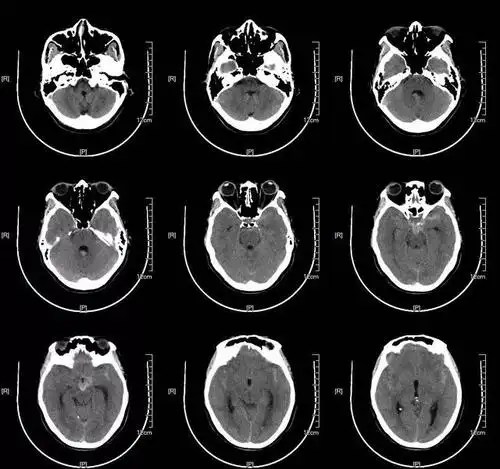

图6. 2017年5月15日头颅ct显示脑沟脑池不清晰,脑肿胀明显.